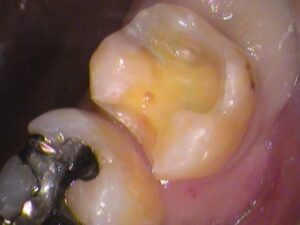

また、

セメントが入っていた内部にも虫歯が広がっていました。

隙間から入り込まれたのか、

以前の虫歯の取り残しなのか、

はっきりとは分かりませんが、虫歯は取り除きましょう。

染色を繰り返しながら、

虫歯を丁寧に取っていきます。